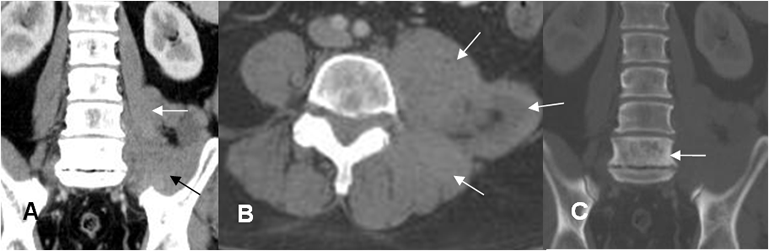

Fig 186 A. Linfoma.

A: TAC reconstrucción coronal y B: TAC axial. Engrosamiento de los músculos psoas y paraespinales en el lado izquierdo.

C: TAC reconstrucción coronal en ventana de hueso. Adicionalmente se identifica esclerosis en el cuerpo de L5, sin destrucción ósea.